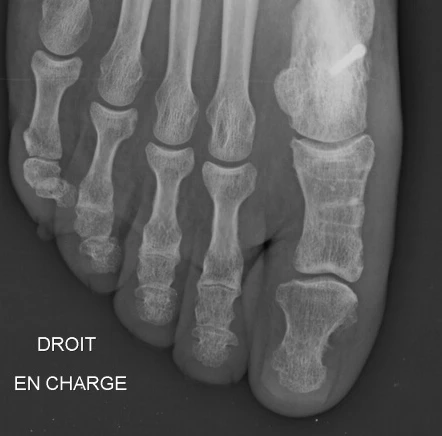

Figure 3: Trigon™ HA Stand-Alone Wedge Fixation System (a) Evans lengthening osteotomies (left) and (b) Cotton (opening wedge) osteotomies of the medial cuneiform (right). The system is manufactured from PEEK-OPTIMA™ HA Enhanced. Images provided courtesy of Nvision Biomedical Technologies. ©Nvision Biomedical Technologies.